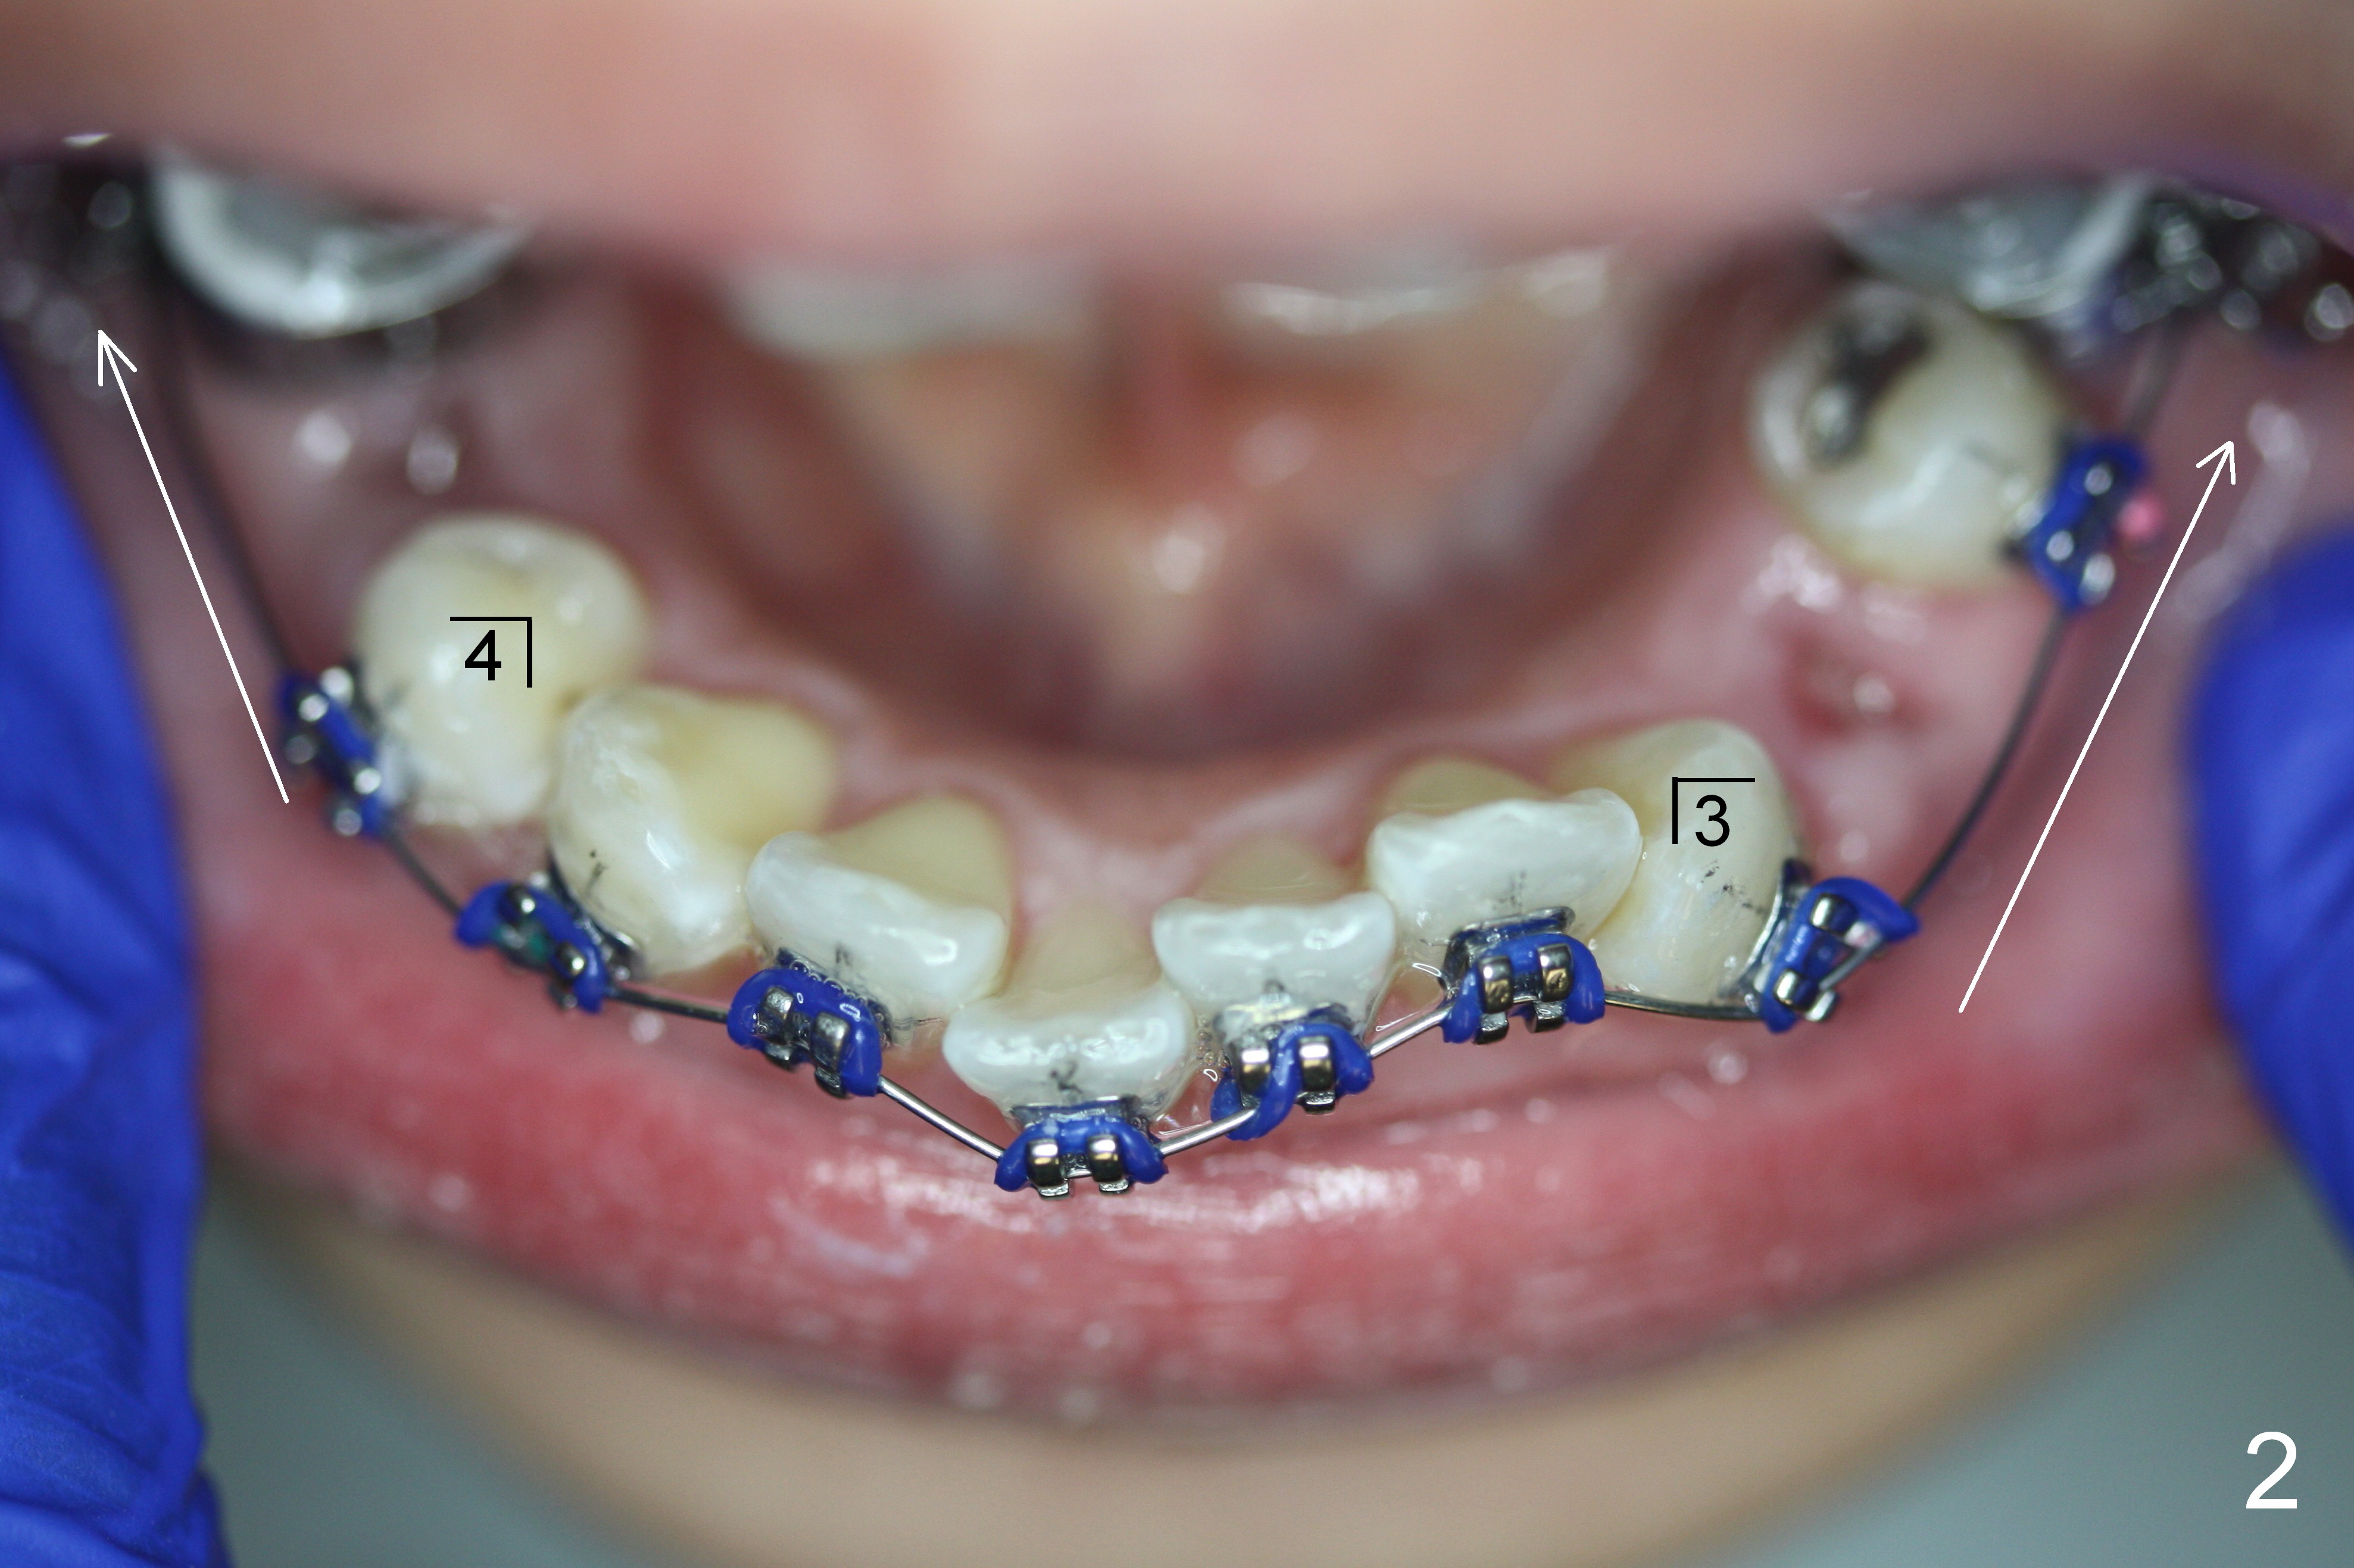

The lower 4s are expected to be extracted. On the day of surgery, LR 5 is found to have been heavily restored (MO amalgam, DO composite, Fig.1); the prognosis is less favorable than LR 4. So the former is extracted (Fig.2).

On the other side, the canine area is crowded (Fig.1: 3). Therefore the lower left 1st bicuspid is extracted (Fig.2). Fig.2 is taken on the day of banding (2 weeks post extraction). A Niti wire (.014") is used. According to model surgery, the anterior teeth are to be distalized (Fig.2 arrows).